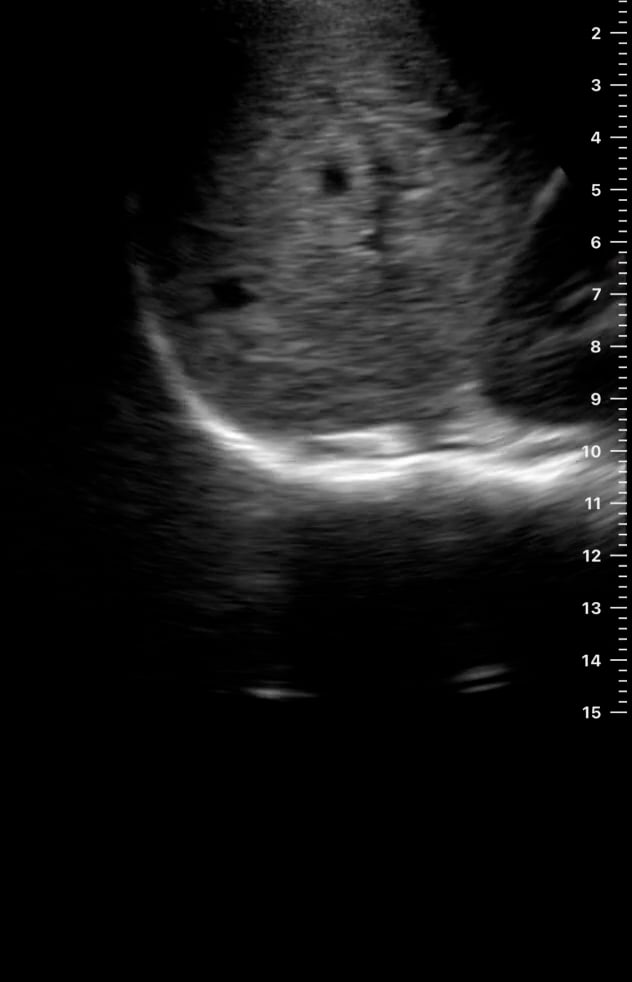

Ascites refers to the abnormal accumulation of fluid within the peritoneal cavity, the space surrounding abdominal organs. In medical imaging, particularly with ultrasound, ascites presents as an anechoic (black) or hypoechoic (dark) fluid collection, often outlining bowel loops or organs. This condition is a key indicator of underlying pathologies such as liver cirrhosis, heart failure, kidney disease, or certain cancers, requiring accurate diagnosis for proper patient management.

Ultrasound is a crucial tool for detecting and quantifying abdominal ascites due to its real-time imaging capabilities and portability. Sonographers can effectively visualize even small amounts of fluid, aiding in diagnostic assessments and guiding therapeutic procedures like paracentesis. Understanding ascites on ultrasound is essential for precise medical diagnosis and optimizing patient care in abdominal evaluations.